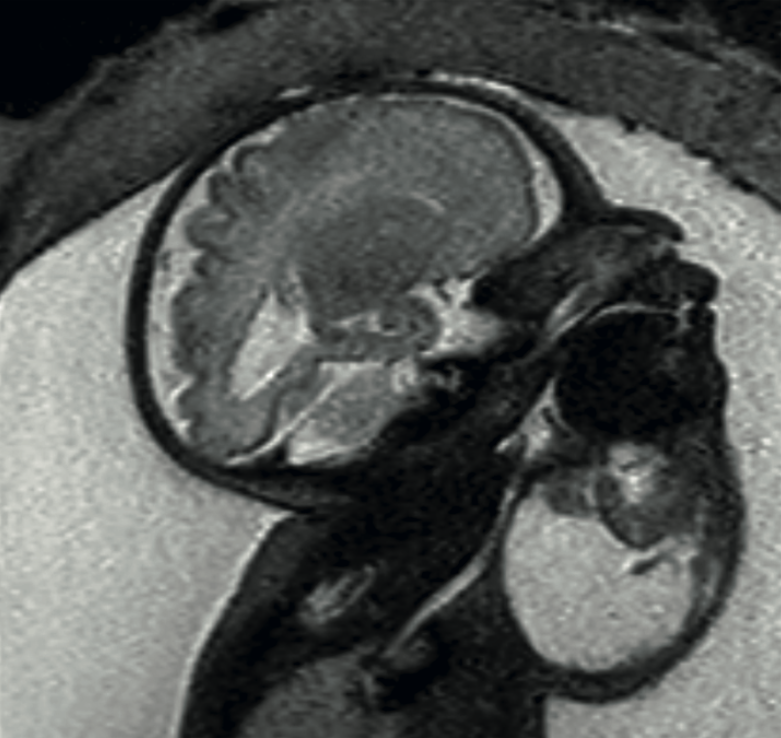

Caso 2

Paciente de 22 años, con diagnóstico de tumoración en el cuello del feto a las 28 semanas, con polihidramnios. En el ultrasonido y la resonancia magnética se observó un tumor en el lado izquierdo y anterior del cuello (5 x 5.9 cm), heterogéneo en su interior, con partes quísticas y sólidas, con aparente vaso nutricio a la aplicación del Doppler. El nacimiento por cesárea se llevó a cabo a las semana 37 semanas, de una niña de 2820 g, Apgar 5-9. Se intubó mediante video-laringoscopia. En el ultrasonido se advirtió una tumoración sólida, y la resección se efectuó a las 48 horas de vida, por teratoma inmaduro. Se dio de alta con indicación de interconsulta. Figura 2

<strong>Figura 2</strong>

Figura 2. Resonancia a las 35 semanas, secuencia T2. Se observa una lesión heterogénea mixta, quística-sólida, en el hemicuello izquierdo, con extensión al piso de la boca y desplazamiento de la vía aérea.